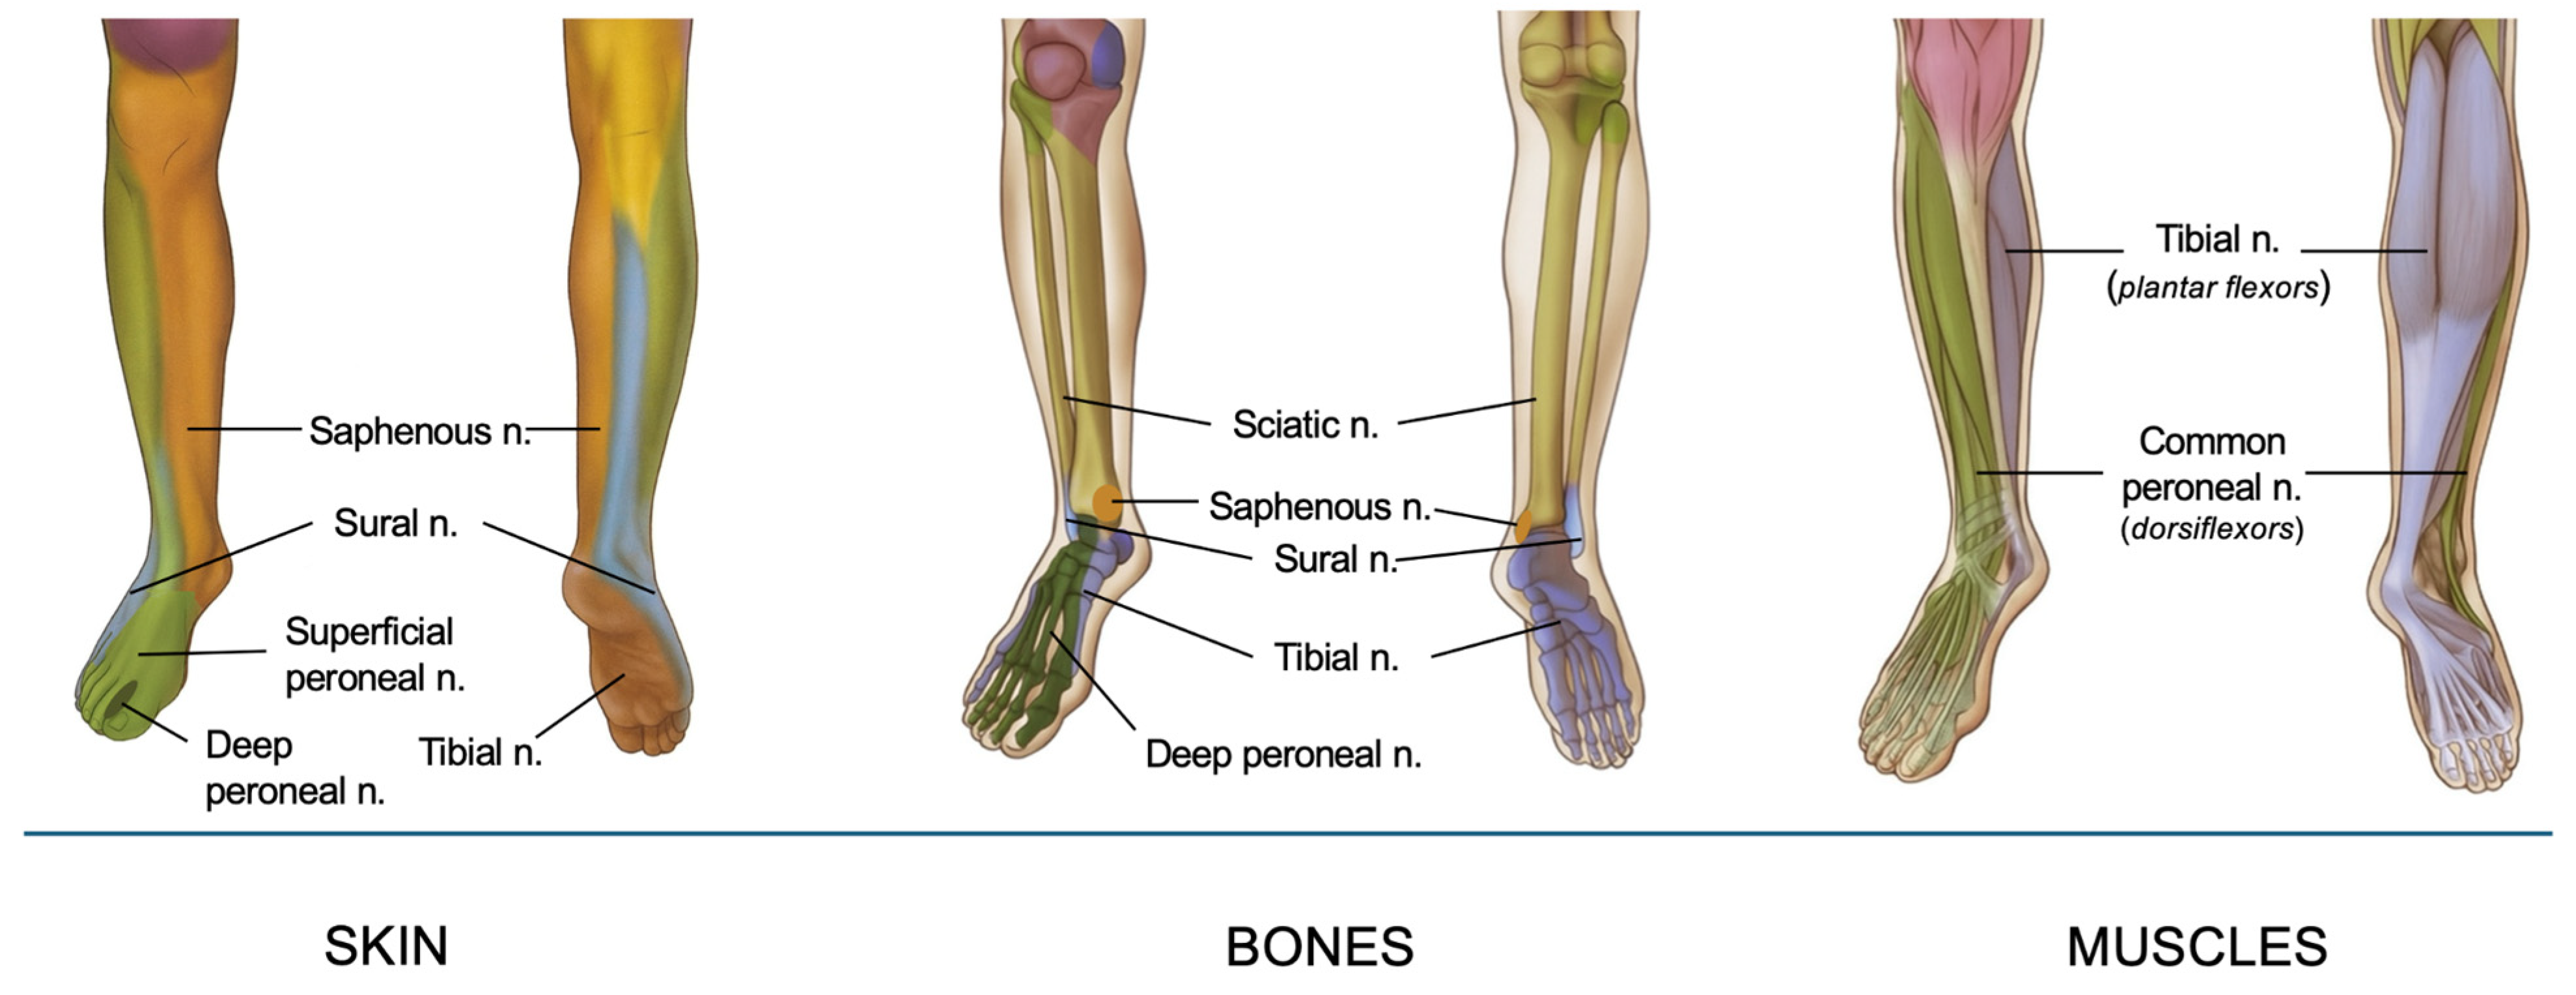

3. Innervation of the Foot and Ankle

The sensory and motor innervation of the foot and ankle is primarily derived from the sciatic and saphenous nerves, branches of the lumbosacral plexus. The sciatic nerve (roots L4-S3) descends through the posterior thigh and bifurcates in the popliteal fossa into the tibial and common peroneal nerves [7]. The tibial nerve descends and passes posterior to the medial malleolus before branching into medial and lateral plantar nerves. The plantar nerves provide sensory innervation to the sole of the foot, and the intrinsic muscles of the foot (e.g., flexor digitorum brevis and abductor hallucis). Specifically, the medial plantar nerve innervates the medial two-thirds of the sole of the foot, and the lateral plantar nerve innervates the lateral third and the small muscles of the foot [2]. The common peroneal nerve wraps around the fibular neck after branching from the sciatic nerve and then derives into the deep peroneal nerve (DPN) and superficial peroneal nerve (SPN). DPN is responsible for motor innervation to the muscles of the anterior compartment of the leg (e.g., tibialis anterior) and sensory innervation to the interdigital space between the first and second toes. SPN provides sensation to the dorsum of the foot and the lateral part of the lower leg and provides motor innervation to the peroneus longus and brevis muscles. The medial side of the foot and ankle are also innervated by the saphenous nerve (sensory branch of the femoral nerve), which is the longest branch of the femoral nerve running along the great saphenous vein. It provides cutaneous sensation to the medial leg, ankle and foot. A comprehensive understanding of this intricate anatomy is essential for effective regional anesthesia, as it allows precise targeting of the nerves responsible for sensory and motor function in the surgical area, optimizing perioperative pain management.

Innervation of foot and ankle is resumed in Figure 1.

A synthesis of foot and ankle innervation, organized by cutaneous, muscular, and bony structures.

Figure 1. Innervation of foot and ankle.